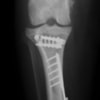

術前写真

手術前後のTPA(脛骨高平部の角度)を測定しています。

約29°から約10°へ矯正されています。